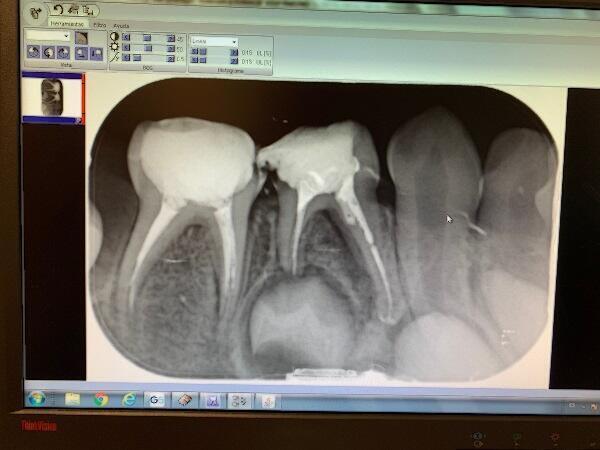

La pulpectomia en nens és un tractament que es prescriu quan hi ha una afectació irreversible del nervi o una necrosis (mort) d’aquest. En ocasions, a més, el pacient pot presentar un micró abscés amb pus, signe de la degeneració pulpar de la dent.

Mitjançant aquest tractament, el dentista infantil elimina el teixit nerviós malalt (popularment conegut com “el nervi”) de la corona dental i també de les arrels. Dit d’una altra forma, treu tot el teixit inflamat i infectat de tota la dent. D’aquesta manera, s’aconsegueix mantenir la dent a la boca, però sense el nervi. Els conductes on es troba el teixit nerviós s’omplen amb un material que segella les arrels. Aquest material anirà desapareixent a mesura que les dents permanents empenyin per aparèixer a nivell gingival (“erupcionen”, “surten”).

La pulpotomia és un tractament indicat en dents primàries amb càries profundes i/o infecció o inflamació superficial que només afecta a la part del nervi més superficial (a la corona de la dent). El problema es troba a la zona coronal, però a diferència de la pulpectomia, el nervi de la zona radicular encara no està malmès.

El procediment consisteix en l’eliminació de la polpa coronal afectada, deixant teixit nerviós a les arrels. A més, es col·loca un material a nivell de l’entrada dels conductes radiculars amb la finalitat de preservar la polpa radicular sense patologia.

La principal diferència entre els procediments de pulpotomia i pulpectomia en dents temporals es troba en la quantitat de teixit pulpar eliminat. En el cas de la pulpotomia és parcial, donat que es retira la zona pulpar més “superficial”, mentre que, en la pulpectomia, la remoció del teixit nerviós és total. Per tant, en aquest últim cas, es duu a terme a la corona i les arrels de la dent temporal.

La decisió de dur a terme un tractament o altre la prendrà l’Odontopediatra especialitzat en pulpotomia i pulpectomia, de mutu acord amb la família del pacient. Per tant, es farà segons un diagnòstic clínic i radiogràfic, previ a l’avaluació del pronòstic de la dent.